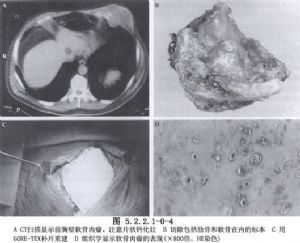

除病史及體格檢查外,還要攝胸部X線片,斷層攝影等必要的檢查。胸壁軟組織腫瘤X線片的特點爲陰影密度不高。切線位片瘤體中心位於側胸壁,瘤體與胸壁成鈍角。骨良性腫瘤一般爲圓形、橢圓形,骨皮質無斷裂。骨軟骨瘤常見在肋骨骨髓區內,頂部呈圓形或菜花狀,境界銳利,有不規則鈣化軟骨帽,瘤內有點狀鈣化。軟骨瘤常發生在肋骨與肋軟骨交界處,腫瘤有分葉,受累骨膨脹,骨皮質變薄,內有點狀鈣化,難與軟骨肉瘤鑑別。骨纖維結構不良,常發生在後側肋骨,始自嬰幼兒期,常到青壯年才發現,病竈呈侷限性膨大,骨皮質變薄,病變區呈磨玻璃樣變。肋骨骨鉅細胞瘤有皁泡狀透亮區,骨皮質薄如蛋殼。惡性腫瘤X線所見,主要爲侵蝕性骨破壞,呈篩孔樣、蟲蝕樣,可見溶骨或成骨性改變,邊緣較毛糙,骨皮質缺損、中斷或病理性骨折。軟骨肉瘤起自骨髓部分,呈分葉狀腫塊,邊緣不清,內有點狀或斑狀鈣化竈。骨肉瘤X線表現分爲溶骨型、成骨型及混合型3種。成骨型有放射狀排列的新生針狀骨小梁,邊界不清。Ewing肉瘤佔原發性胸壁骨腫瘤的12%,X線片見骨呈斑片狀破壞,含有溶骨和增生區,骨膜增生呈層狀,稱“蔥皮”樣改變。MRI可將腫瘤與血管區別,應採用不同平面瞭解腫瘤情況。活檢是診斷的可靠方法,應注意惡性腫瘤常有良性部分,多部位、足夠組織取材是正確診斷的關鍵。胸壁腫瘤的診斷十分重要,它決定治療方法的選擇(圖5.2.2.1-0-1~5.2.2.1-0-5)。

人工材料可自由設計取材,不受大小的限制,但有異物反應,易感染,不能隨呼吸運動伸展,可有鬆脫、破裂及發生疼痛的缺點。故目前對金屬、有機玻璃、硅橡膠等人工材料已漸棄用。聚四氟乙烯(Gore-Tex)片是較好的胸壁重建材料,抗張能力強,切割縫合均較方便,具有一定的組織相容性及抗感染能力,發生感染後亦不必取出。